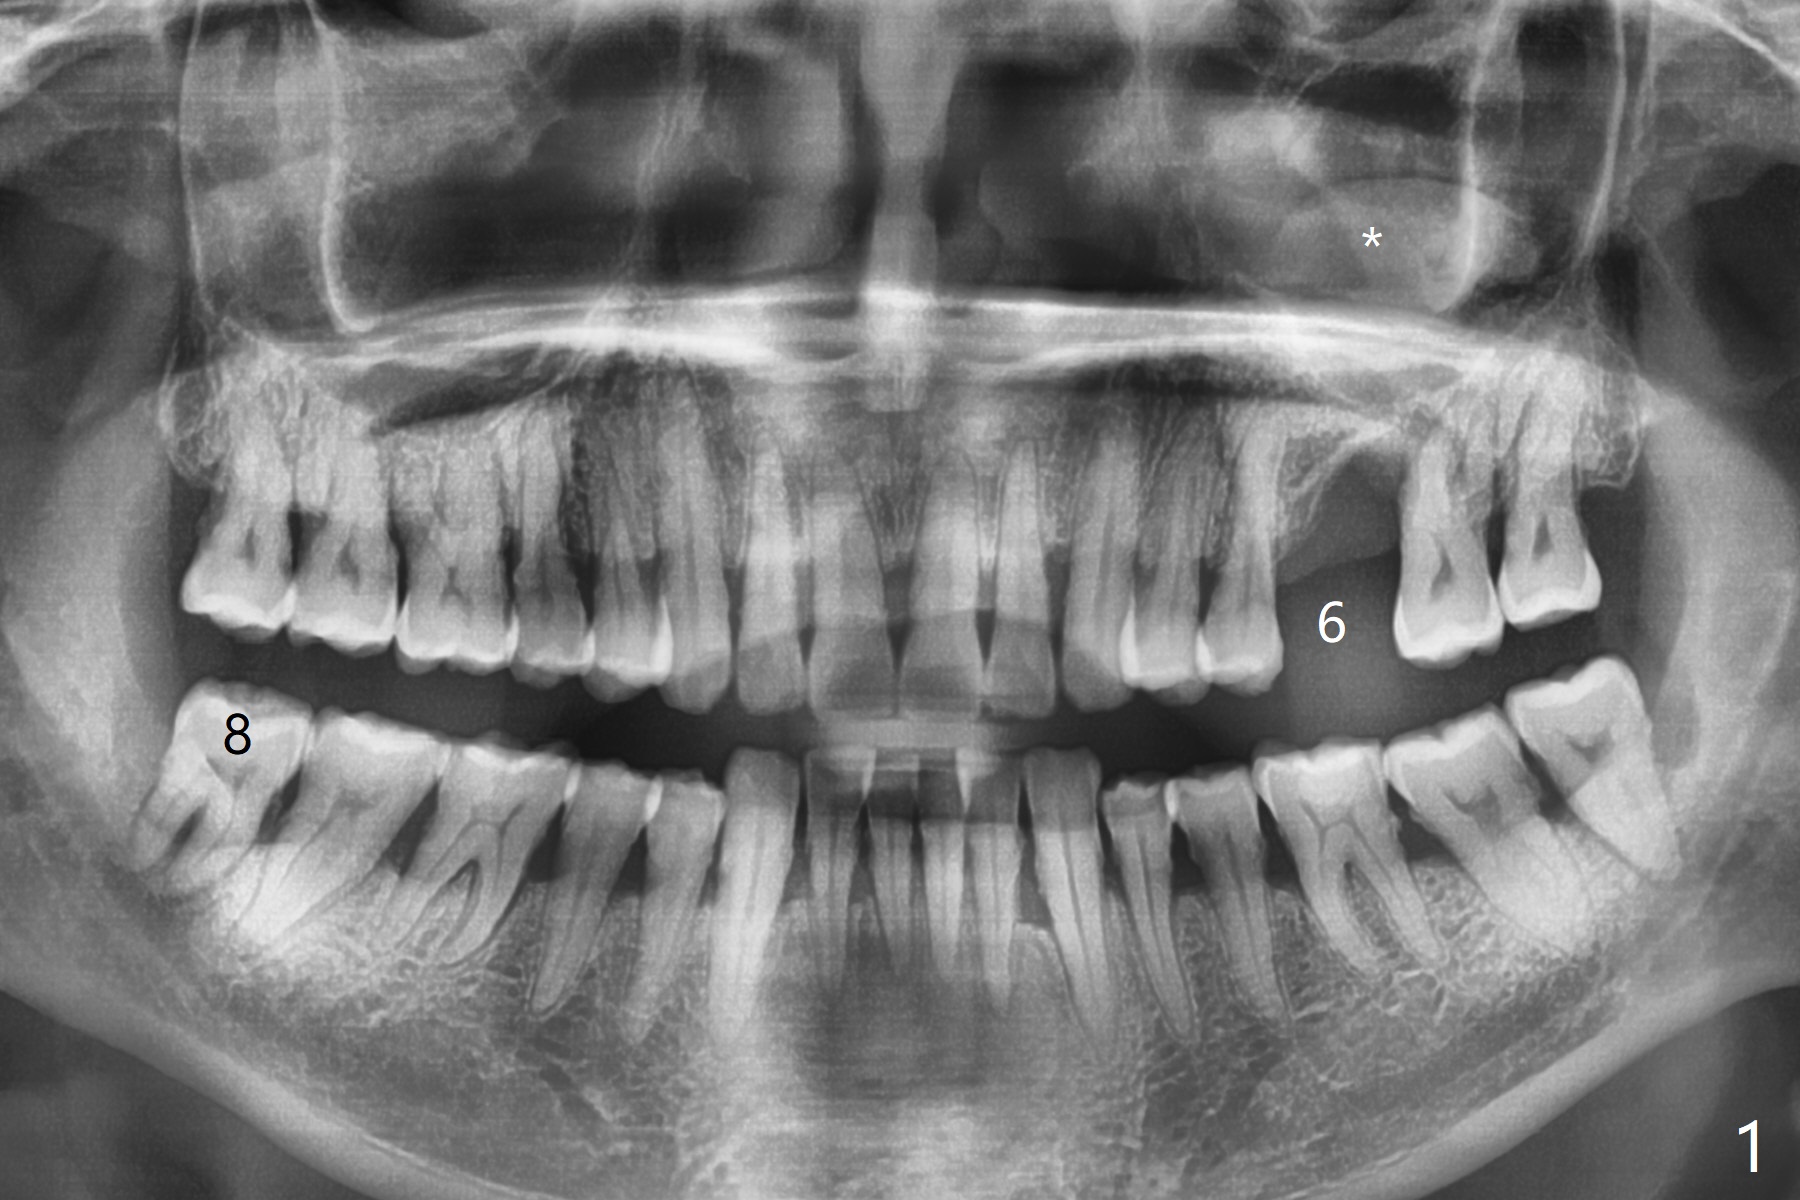

47岁男(吸烟一天半包)因右下8疼痛就诊,口服抗生素疼痛消失,不愿意拔除,但是要求左上6植牙(图一),左上颌窦好像有粘液囊肿(图一,三:*),而右侧上颌窦粘膜更厚(图二)。左上6植牙床是一个斜面,植牙会远中偏移,导板设计应有意往近中(图三:红线)。植体远中根尖需要内提升,冠部需要植骨(图四),厚的粘骨膜有利于植骨(粘骨,使用mill abutment),骨粉尽可能放置7牙根近中(图五:红色圆圈,Endogain)。第二种设计(图六)使用细长植体,近中龈下4毫米,远中龈下8毫米,有利于植骨,覆盖远中暴露的螺纹。Return to No Caries 位点保存/导板 手术 提升 Xin Wei, DDS, PhD, MS 1st edition 10/28/2020, last revision 04/04/2021